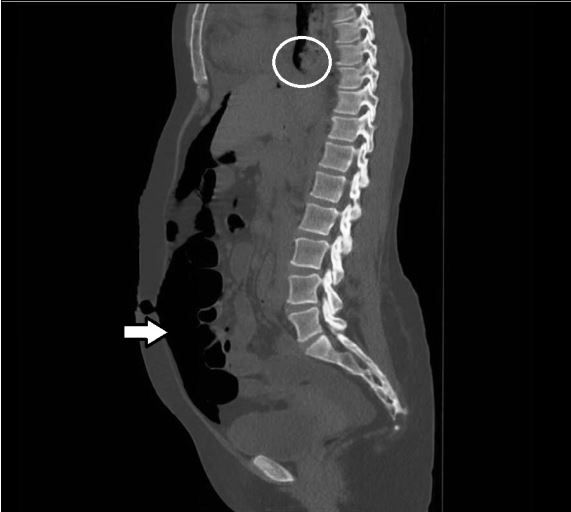

CT scans of the patient’s chest, abdomen, and pelvis further detailed the pneumoperitoneum and showed intraluminal free air alongside gravity-defying intramural air in the small intestine, although there were no signs of perforation (Figure 2). Of note, the radiographs revealed esophageal stricture with proximal dilatation in addition to pneumoperitoneum, consistent with the patient’s diagnosis of scleroderma (Figure 3).